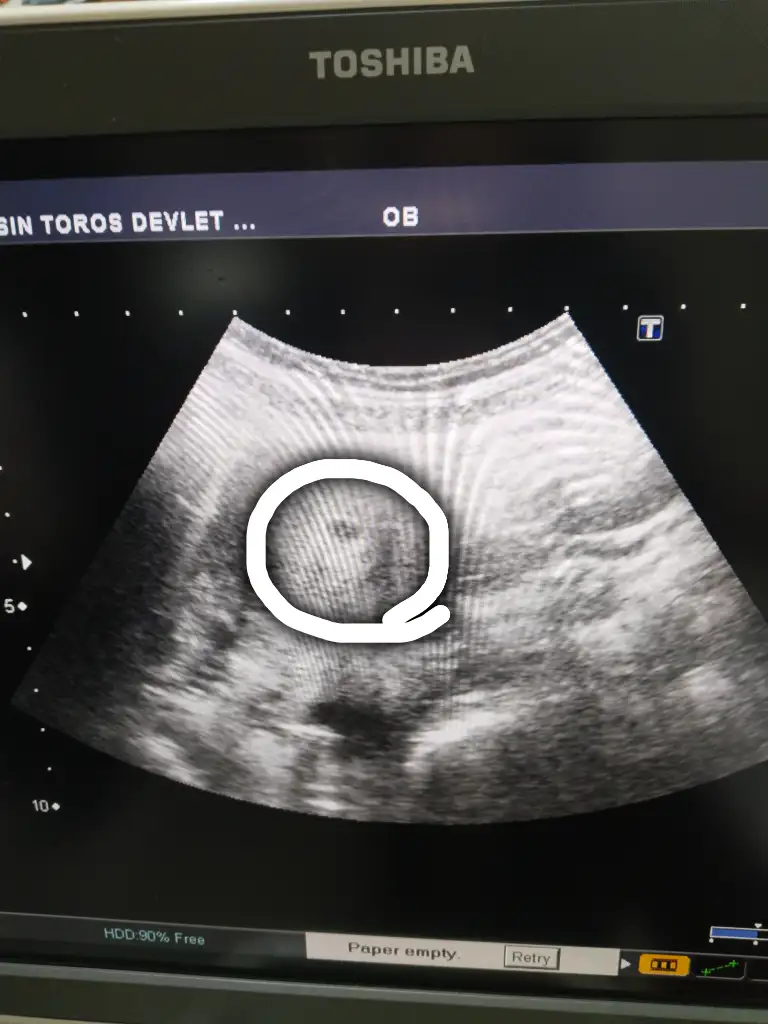

Çok şükür bugün keseyi gördük herşey normal 2 hafta sonra kalp sesi için çağırdıHayırlı olsun nasılsın oldu şimdi

Saglıkla kucağjna aldırsın Allah ccÇok şükür bugün keseyi gördük herşey normal 2 hafta sonra kalp sesi için çağırdı